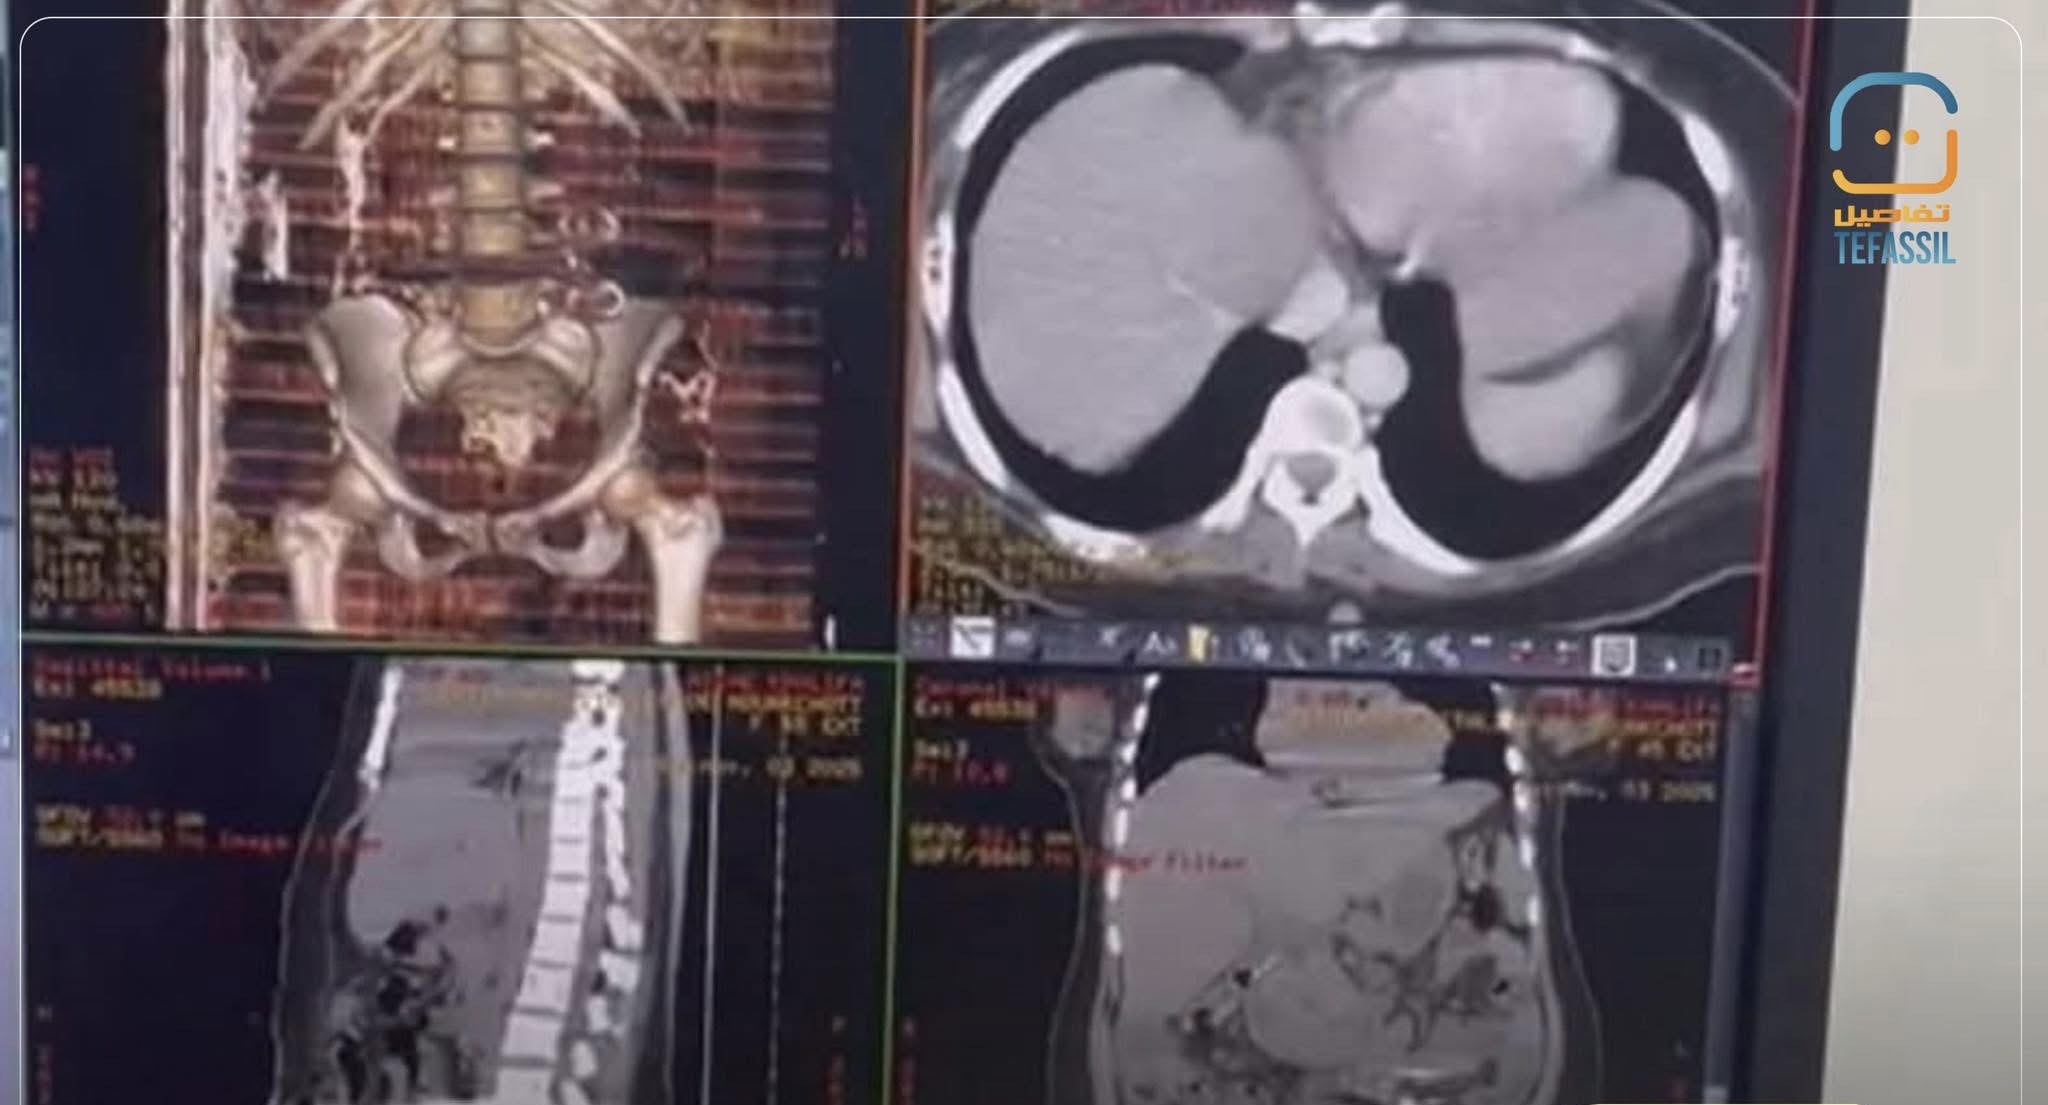

نجح طاقم طبي من المستشفى الوطني في نواكشوط من استخراج مقص جراحي من بطن سيدة تبلغ من العمر 45 عامًا، كانت قد خضعت قبل عشرين يومًا لعملية استئصال ورم ليفي رحمي في السنغال، بعد معاناتها من آلام حادة ومستمرة كشفت الأشعة المقطعية سببها.